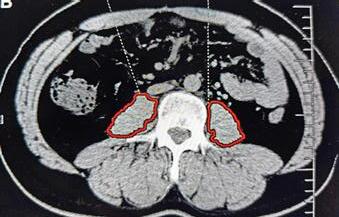

la pacienții cu masă musculară scăzută și/sau coeficient scăzut de atenuare CT a masei musculare, aflați sub imunoterapie15